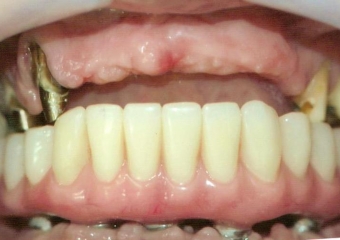

Próteses fixas definitivas em resina em Outubro de 2016 - Clínica Cliniface

Próteses fixas definitivas em resina em Outubro de 2016